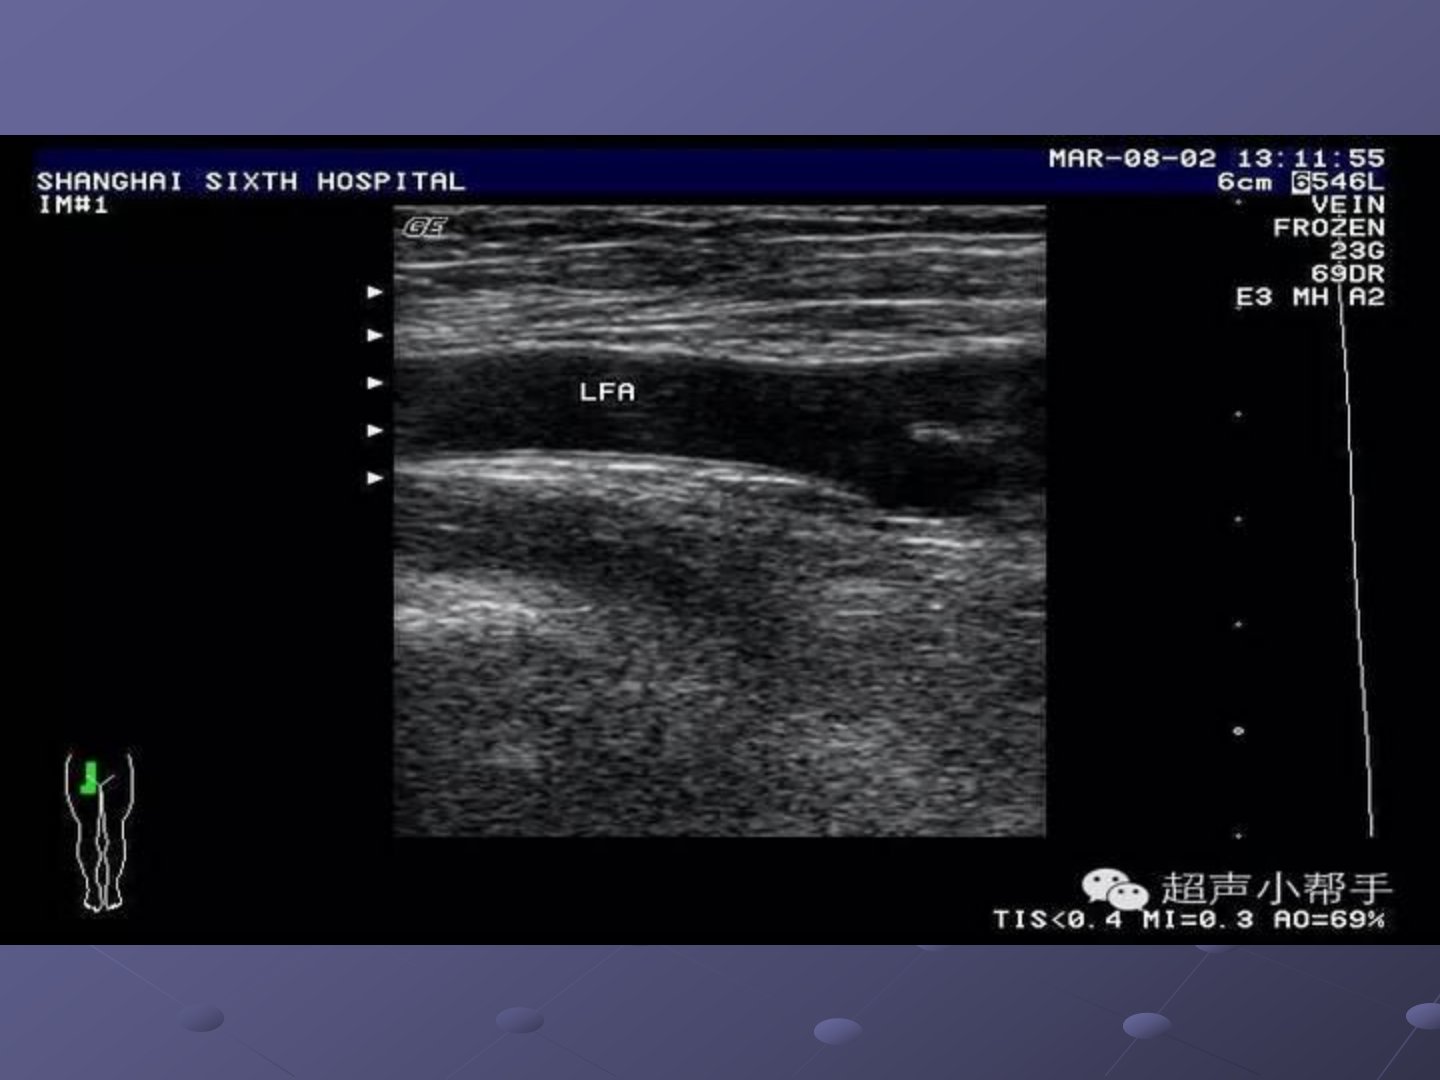

四肢血管超声诊断杨定叶四肢血管超声诊断一.四肢血管彩色多普勒检查适应症:1、动脉系统疾病:(1) 动脉硬化性闭塞,显示斑块大小,管腔狭窄程度。(2) 急性动脉栓塞和动脉血栓形成,可显示栓塞部位及程度,为外科手术提供有用信息。(3) 动脉瘤(真性、假性、夹层)及动-静脉瘘。(4) 动脉炎,包括血栓闭塞性脉管炎、多发性大动脉炎等。(5)动脉手术后随访观察,包括人造血管移植及栓塞治疗等,可观察人造血管通畅情况,有无血栓形成。2、静脉系统:(1) 深静脉栓塞,鉴别肢体肿胀的原因是否由于深静脉栓塞所致。可观察栓塞的程度(完全性或不完全性)及栓塞范围,还可进行治疗后的随访观察。(2) 对浅静脉曲张者,检查...